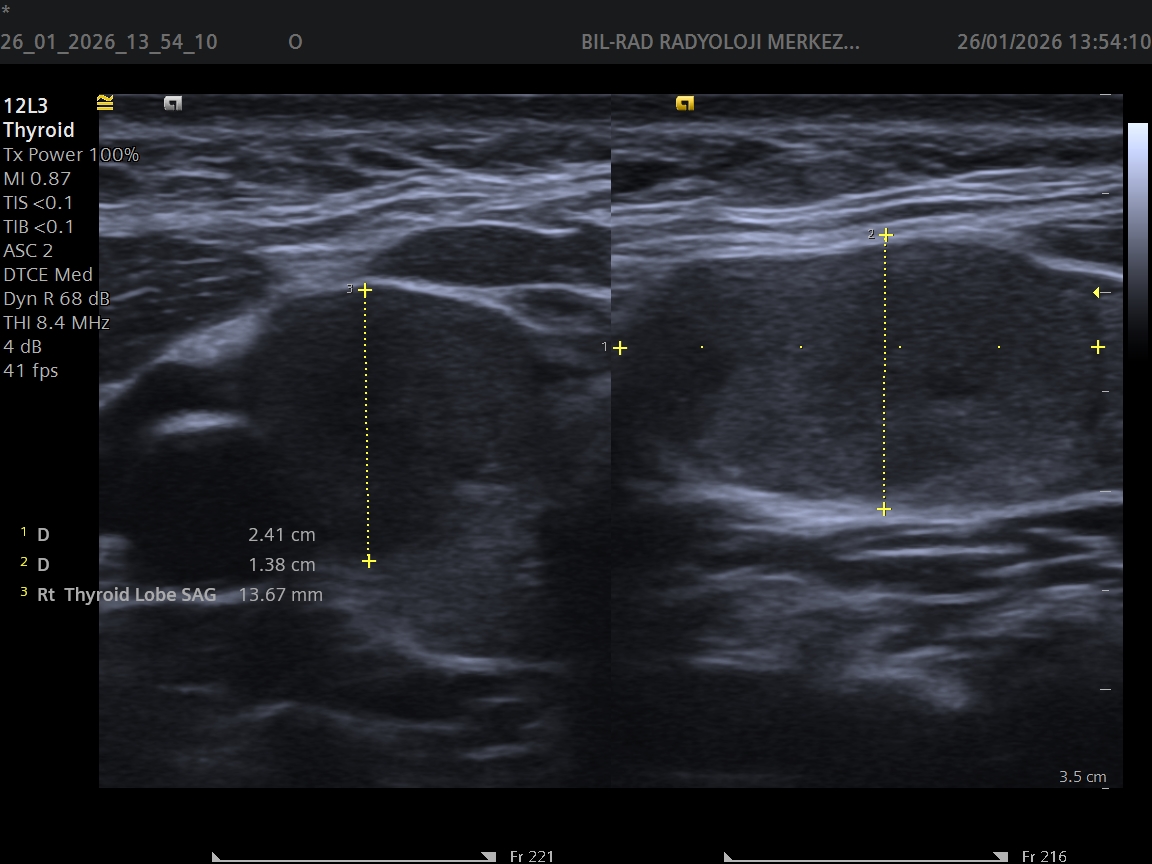

USG Eşliğinde Tiroid Biyopsisi Nedir?

Tiroid nodülü, toplumda oldukça sık görülen bir durumdur. Özellikle kadınlarda ve 40 yaş sonrası bireylerde tiroid bezinde nodül saptanma oranı artar. Mersin'de tiroid nodülü nedeniyle başvuran hastaların en sık sorduğu soru ise şudur: "Bu nodül tehlikeli mi?"